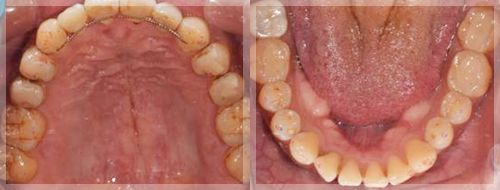

| 術前 |

|---|

![]() ![]() |

主訴:歯が常に当たって痛い、噛む位置が分からない

治療方針

マウスピースを使って正しい噛み合わせを確認し、習慣化させるための診査診断が行われます。口腔内反映とは、マウスピースを装着した状態での正しい噛み合わせを意味し、マウスピースを外すと元の悪い噛み合わせに戻ってしまいます。そこで、仮歯や仮の詰め物を使用して噛み合わせを調整し、マウスピースを外しても正しい位置で噛み合うようにします。

最終的な補綴物として、セラミックやジルコニアなどの素材で被せ物を製作し、治療を完了させます。